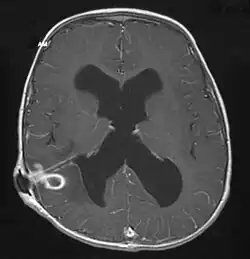

| Brain abscess in a person with a CSF shunt. The abscess is the darker gray region in the lower left of the image (corresponding to the right parietal lobe). The lateral ventricles are visible in black in the center of the brain, adjacent to the abscess.[1] | |

The diagnosis is established by a computed tomography (CT) (with contrast) examination. At the initial phase of the inflammation (which is referred to as cerebritis), the immature lesion does not have a capsule and it may be difficult to distinguish it from other space-occupying lesions or infarcts of the brain. Within 4–5 days the inflammation and the concomitant dead brain tissue are surrounded with a capsule, which gives the lesion the famous ring-enhancing lesion appearance on CT examination with contrast (since intravenously applied contrast material can not pass through the capsule, it is collected around the lesion and looks as a ring surrounding the relatively dark lesion). Lumbar puncture procedure, which is performed in many infectious disorders of the central nervous system is contraindicated in this condition (as it is in all space-occupying lesions of the brain) because removing a certain portion of the cerebrospinal fluid may alter the concrete intracranial pressure balances and causes the brain tissue to move across structures within the skull (brain herniation).[14]